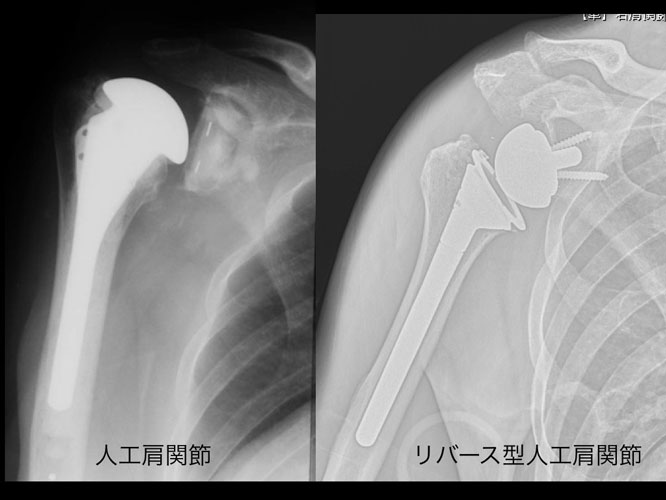

その他の選択肢

- 反転型人工肩関節置換術: 腱板断裂によって関節の機能が破綻している場合に、腱板断裂断裂など、一部のケースで適応される場合があります。

以下は、人工肩関節全置換術(TSA)の中で、「リバース型」を除いたTSAとHAとの比較論文です。

再置換率や臨床成績はTSAがHAよりも明確に優れているエビデンスはないが、腱板が温存されている関節ではTSAの臨床成績と耐久性はHAに比してやや優れており、TSAが主流となっているがHAが悪いというわけではありません。